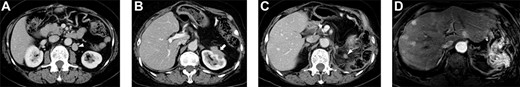

A 71-year-old woman underwent distal pancreatectomy with prophylactic local lymph node resection, left adrenal resection and partial gastric resection for PNEN. The pathological findings of the resected specimen were as follows: well-differentiated NEN, tumor size of 36 mm, negative resection margins, positive vascular invasion, no lymph node metastases and a Ki-67 index of 4%. Four years after the pancreatectomy, abdominal computed tomography (CT) revealed a regional lymph node recurrence located dorsal to the left renal vein (Fig. 1A); therefore, regional lymphadenectomy was performed. The pathological finding was metachronous nodal recurrence of PNEN (Ki-67 index: unknown). Five years after the first surgery, regional lymph node recurrence occurred, with invasion of the left kidney (Fig. 1B); therefore, left nephrectomy with lymphadenectomy was performed. The pathological finding was metachronous nodal recurrence of PNEN (Ki-67 index: 20%) with renal invasion. Five years after the pancreatectomy, follow-up CT and gadoxetic acid–enhanced magnetic resonance imaging (MRI) revealed local recurrence and multiple liver metastases (Fig. 1C and D). Daily oral sunitinib (37.5 mg) was initiated 5 years and 5 months after pancreatectomy; however, the patient developed fever and joint pain 2 weeks after initiating sunitinib. Therefore, sunitinib was switched to daily oral everolimus (10 mg). She maintained stable disease for 1 year and 3 months after the initiation of everolimus; however, follow-up CT revealed enlargement of multiple liver metastases. Therefore, everolimus was switched to weekly streptozocin (800 mg/m2). She maintained stable disease for 1 year and 6 months after the initiation of streptozocin. Streptozocin was switched to sunitinib with lanreotide because of the enlargement of multiple liver metastases. Sunitinib with lanreotide was administered for 1 year and was switched to amrubicin (30 mg/m2) 3 days per week due to the enlargement of multiple liver metastases. The patient died of liver metastases 10 years after pancreatectomy.

Selected abdominal computed tomography and gadoxetic acid–enhanced magnetic resonance images: Case 1. (A) Recurrence for the first time: para-aortic mass measuring 28 mm located dorsal to the left renal vein (arrowhead). (B) Recurrence for the second time: mass measuring 40 mm invading the left kidney (arrow). (C, D) Recurrence for the third time: mass measuring 12 mm at the same site as that of the second recurrence (c; arrowhead) and multiple liver metastases in the bilateral lobe (d).